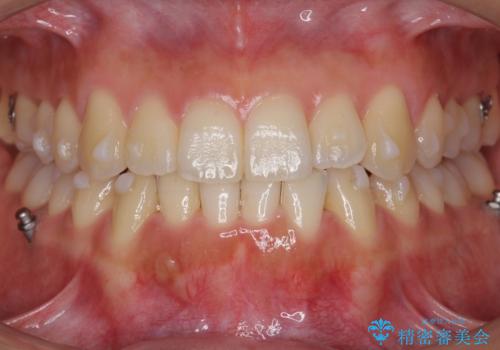

前歯のがたつき インビザラインで 下の奥歯を後ろに下げる

- 上下の前歯のがたつきを主訴に来院。

骨格的に受け口の傾向があり、下の奥歯が前方にに位置しており、下の前歯が特にがたつきが大きい状態でした。

下の奥歯を後ろに下げて下の前歯が前方に出ないように治療しました。

矯正用ミニスクリューを用いて治療しています。